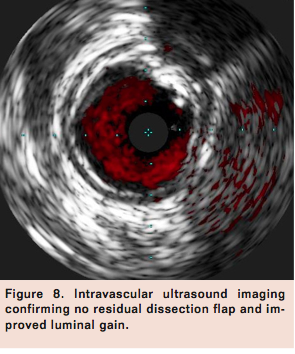

Access was obtained in the left common femoral artery (CFA) and a 7 Fr Pinnacle Destination sheath (Terumo) was positioned across the aortic bifurcation in the right CFA. Selective angiogram of the right lower extremity confirmed mid to distal 80% calcified stenosis of the right SFA (Figure 1), mild popliteal artery disease, and 2-vessel run-off into the right foot. A Grand Slam Wire (Abbott Vascular) was advanced across the right SFA lesion into the distal peroneal artery after anticoagulation with intravenous heparin. Intravascular ultrasound (IVUS) imaging (Volcano) was performed to determine the burden and character of the plaque, which confirmed a severe calcific and eccentric stenosis in the mid SFA (Figure 2). Rotational atherectomy with aspiration thrombectomy was performed using a Jetstream 2.1/3.0 atherectomy catheter (Bayer HealthCare) with four passes across the lesion, two with blades down and two with blades up (Figure 3). Follow-up angiography displayed improved flow but with a non-flow-limiting dissection within the treated segment of the right SFA (Figure 4). Repeat IVUS imaging confirmed an intimal flap consistent with post-atherectomy dissection (Figure 5). Nitinol-constrained balloon angioplasty was performed using a 5 mm x 80 mm over-the-wire Chocolate PTA balloon catheter (TriReme Medical) with a prolonged expansion over 2 minutes (Figure 6). Final angiogram demonstrated excellent angiographic result with brisk flow through the treated segment (Figure 7) and preserved run-off into the foot. Final IVUS imaging confirmed no residual dissection flap and improved luminal gain (Figure 8).